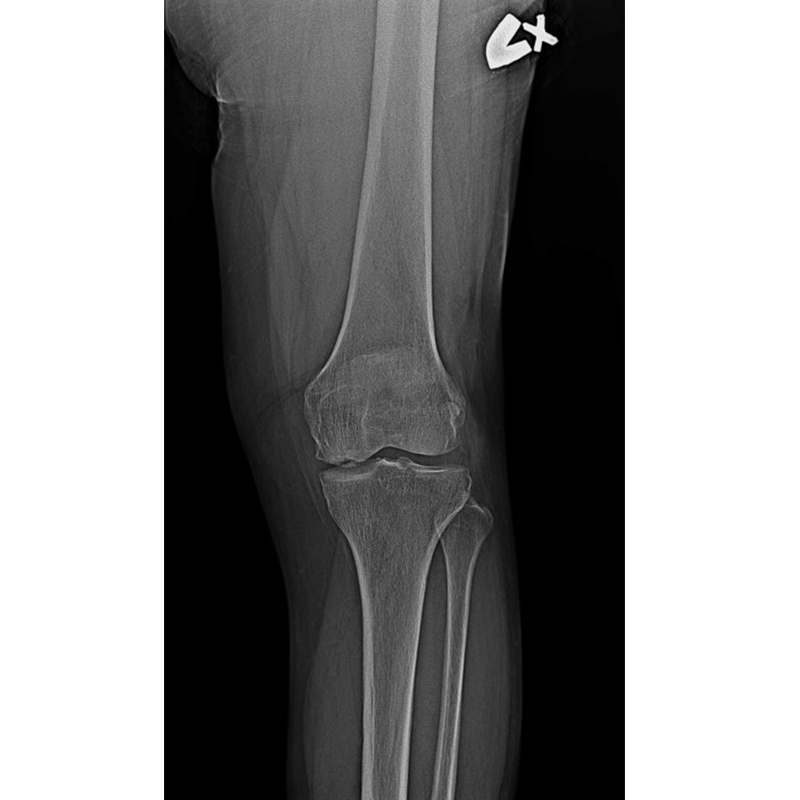

傳統部分膝置換 首頁 案例分享 膝關節手術 傳統部分膝置換 殷女士 65歲 術前 術後 張女士 71歲 術前 術後 蔡女士 74歲 術前 術後 張女士71歲 術前 術後 翁女士70歲 術前 術後 劉女士 80歲 術前 術後